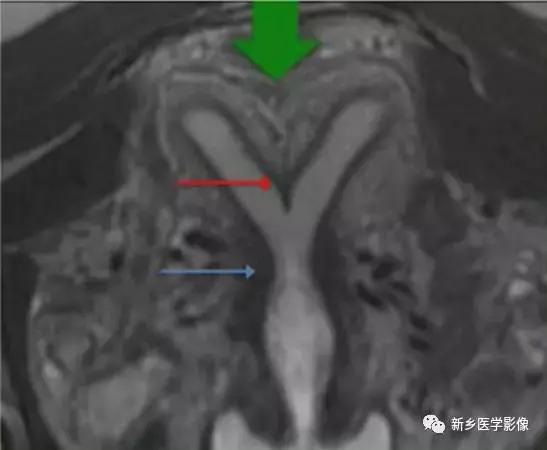

上图:双子宫:双侧子宫及宫颈完全分离

双子宫:双侧子宫完全分离,右侧阴道积血(阴道斜隔),宫腔积血,呈长T2信号。

右侧先天性肾缺如。